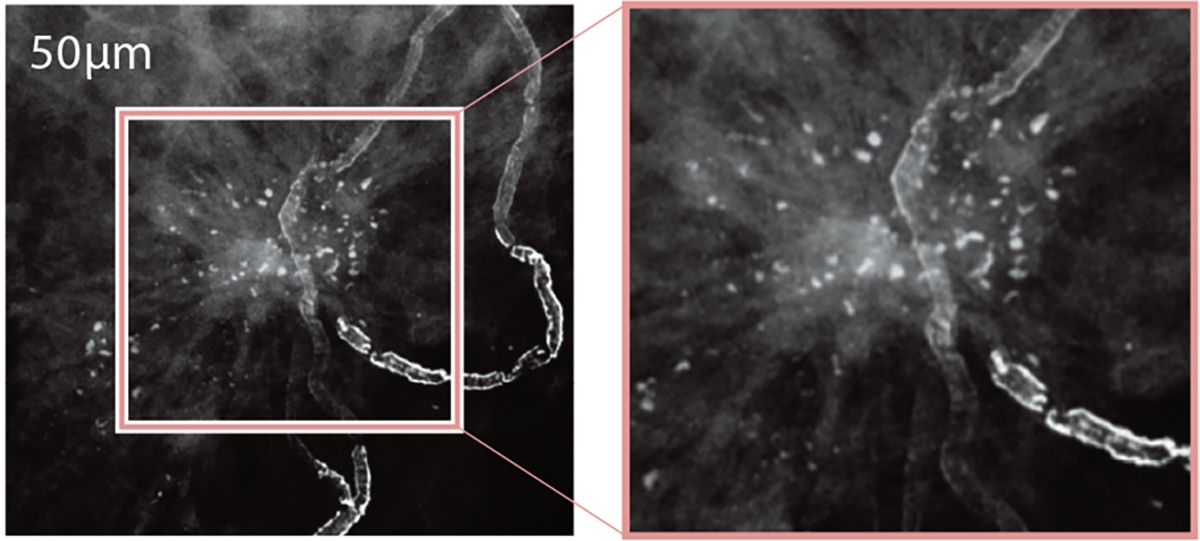

![[photo] Close-up view of Biopsy Positioner - 50μm image solution](https://asset.fujifilm.com/www/nz/files/2020-05/fdf0aa3bc696fa3fc0e37012789e10e6/pic_amulet-innovality_02.jpg)

- Variable image resolution for different needs